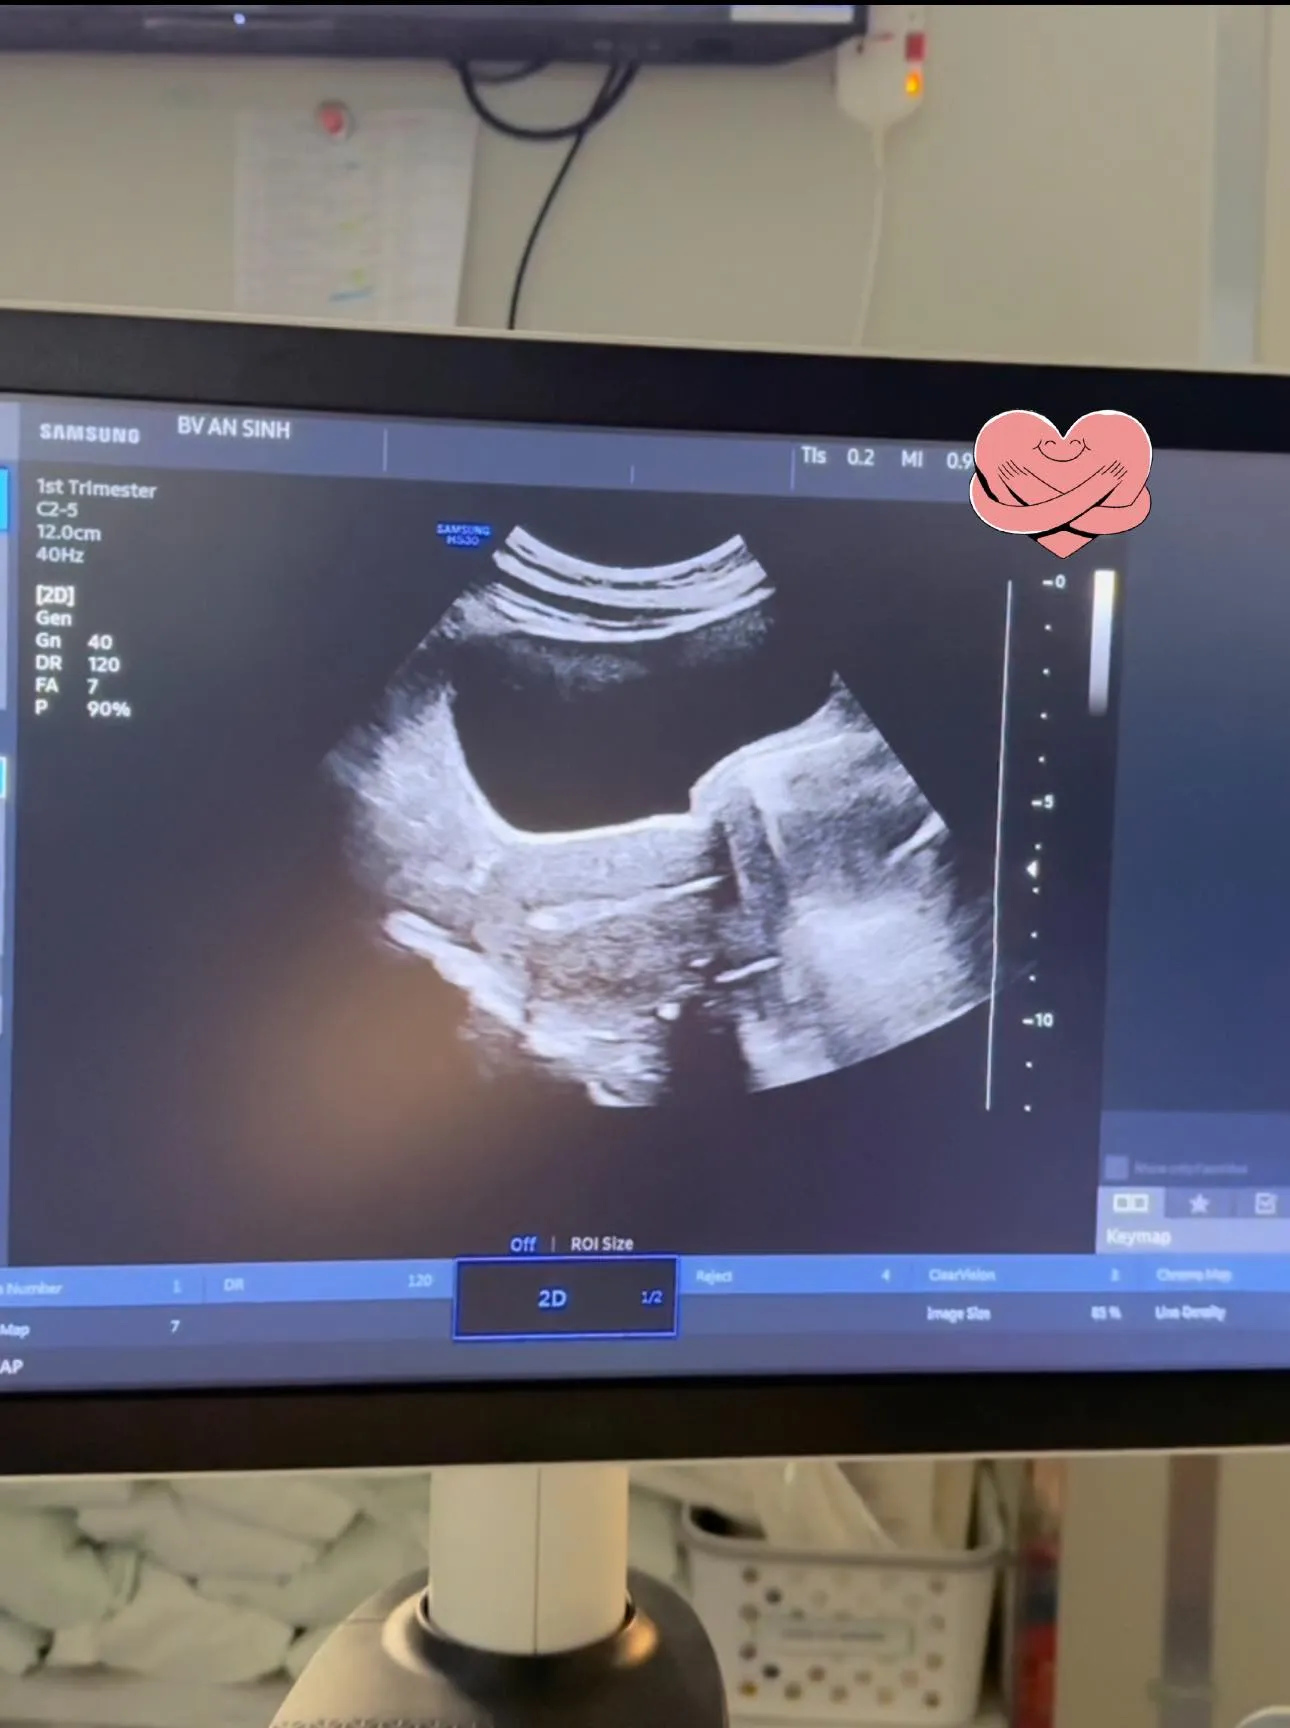

Mới đây, nữ doanh nhân hạnh phúc chia sẻ trên trang cá nhân hình ảnh đi chuyển phôi thai. Cô tiết lộ: "Đón 2 bé phôi về với mẹ nào. Bám mẹ chắc nha 2 đứa ơi" - khiến nhiều người cho rằng Đoàn Di Băng đã chuyển phôi thành công và dự kiến sẽ sinh đôi.